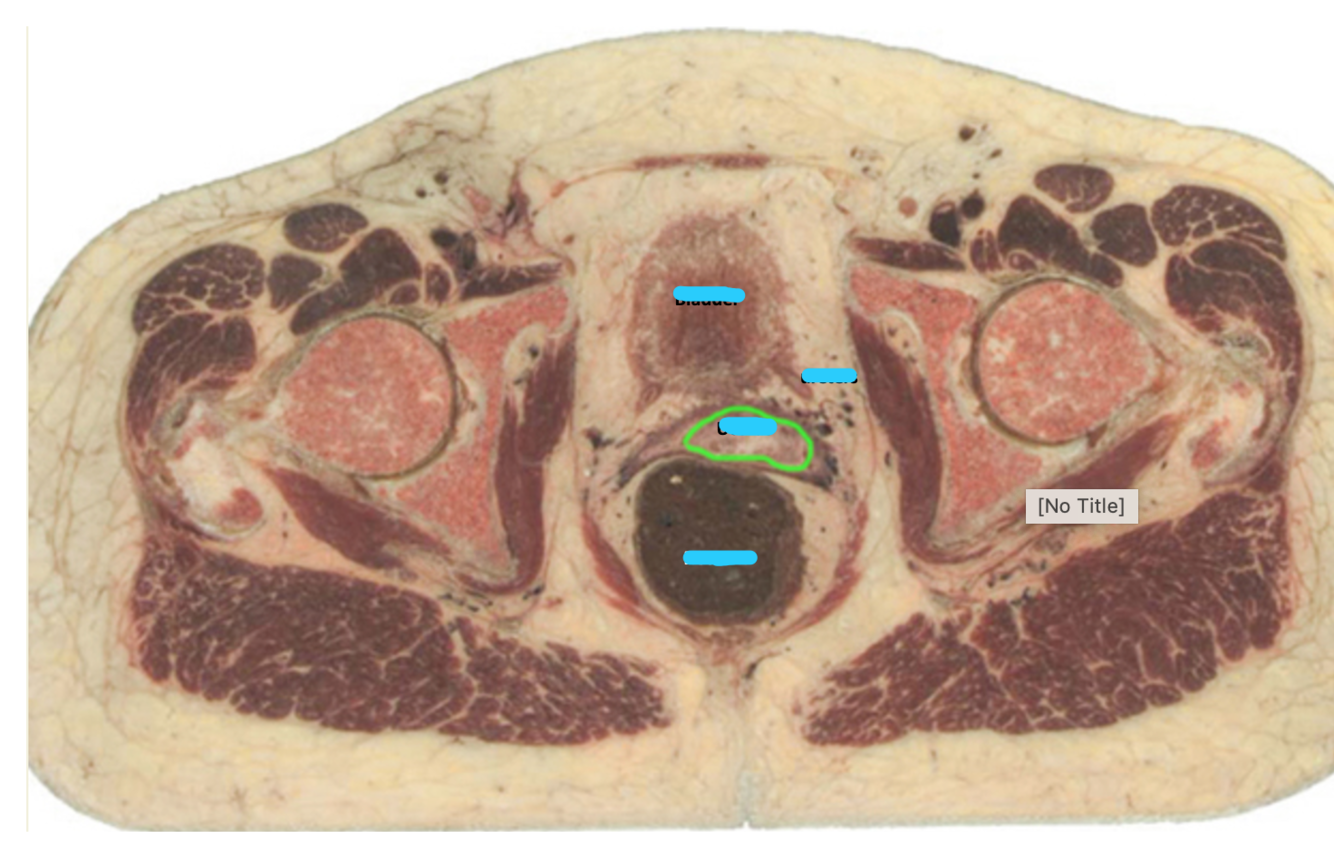

Name the vesicles (blue) and structure (green)